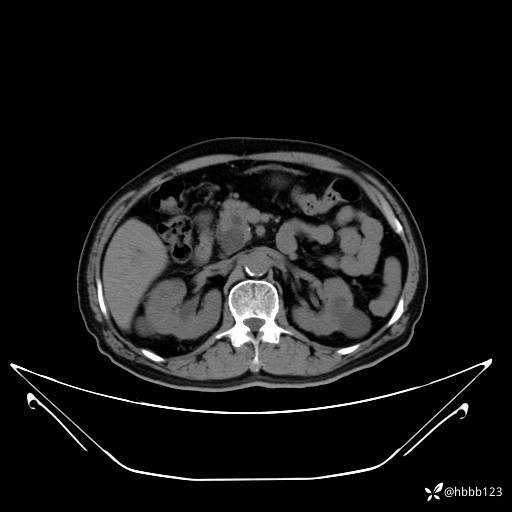

门诊完善上腹部CT平扫+增强扫描:

延迟期: